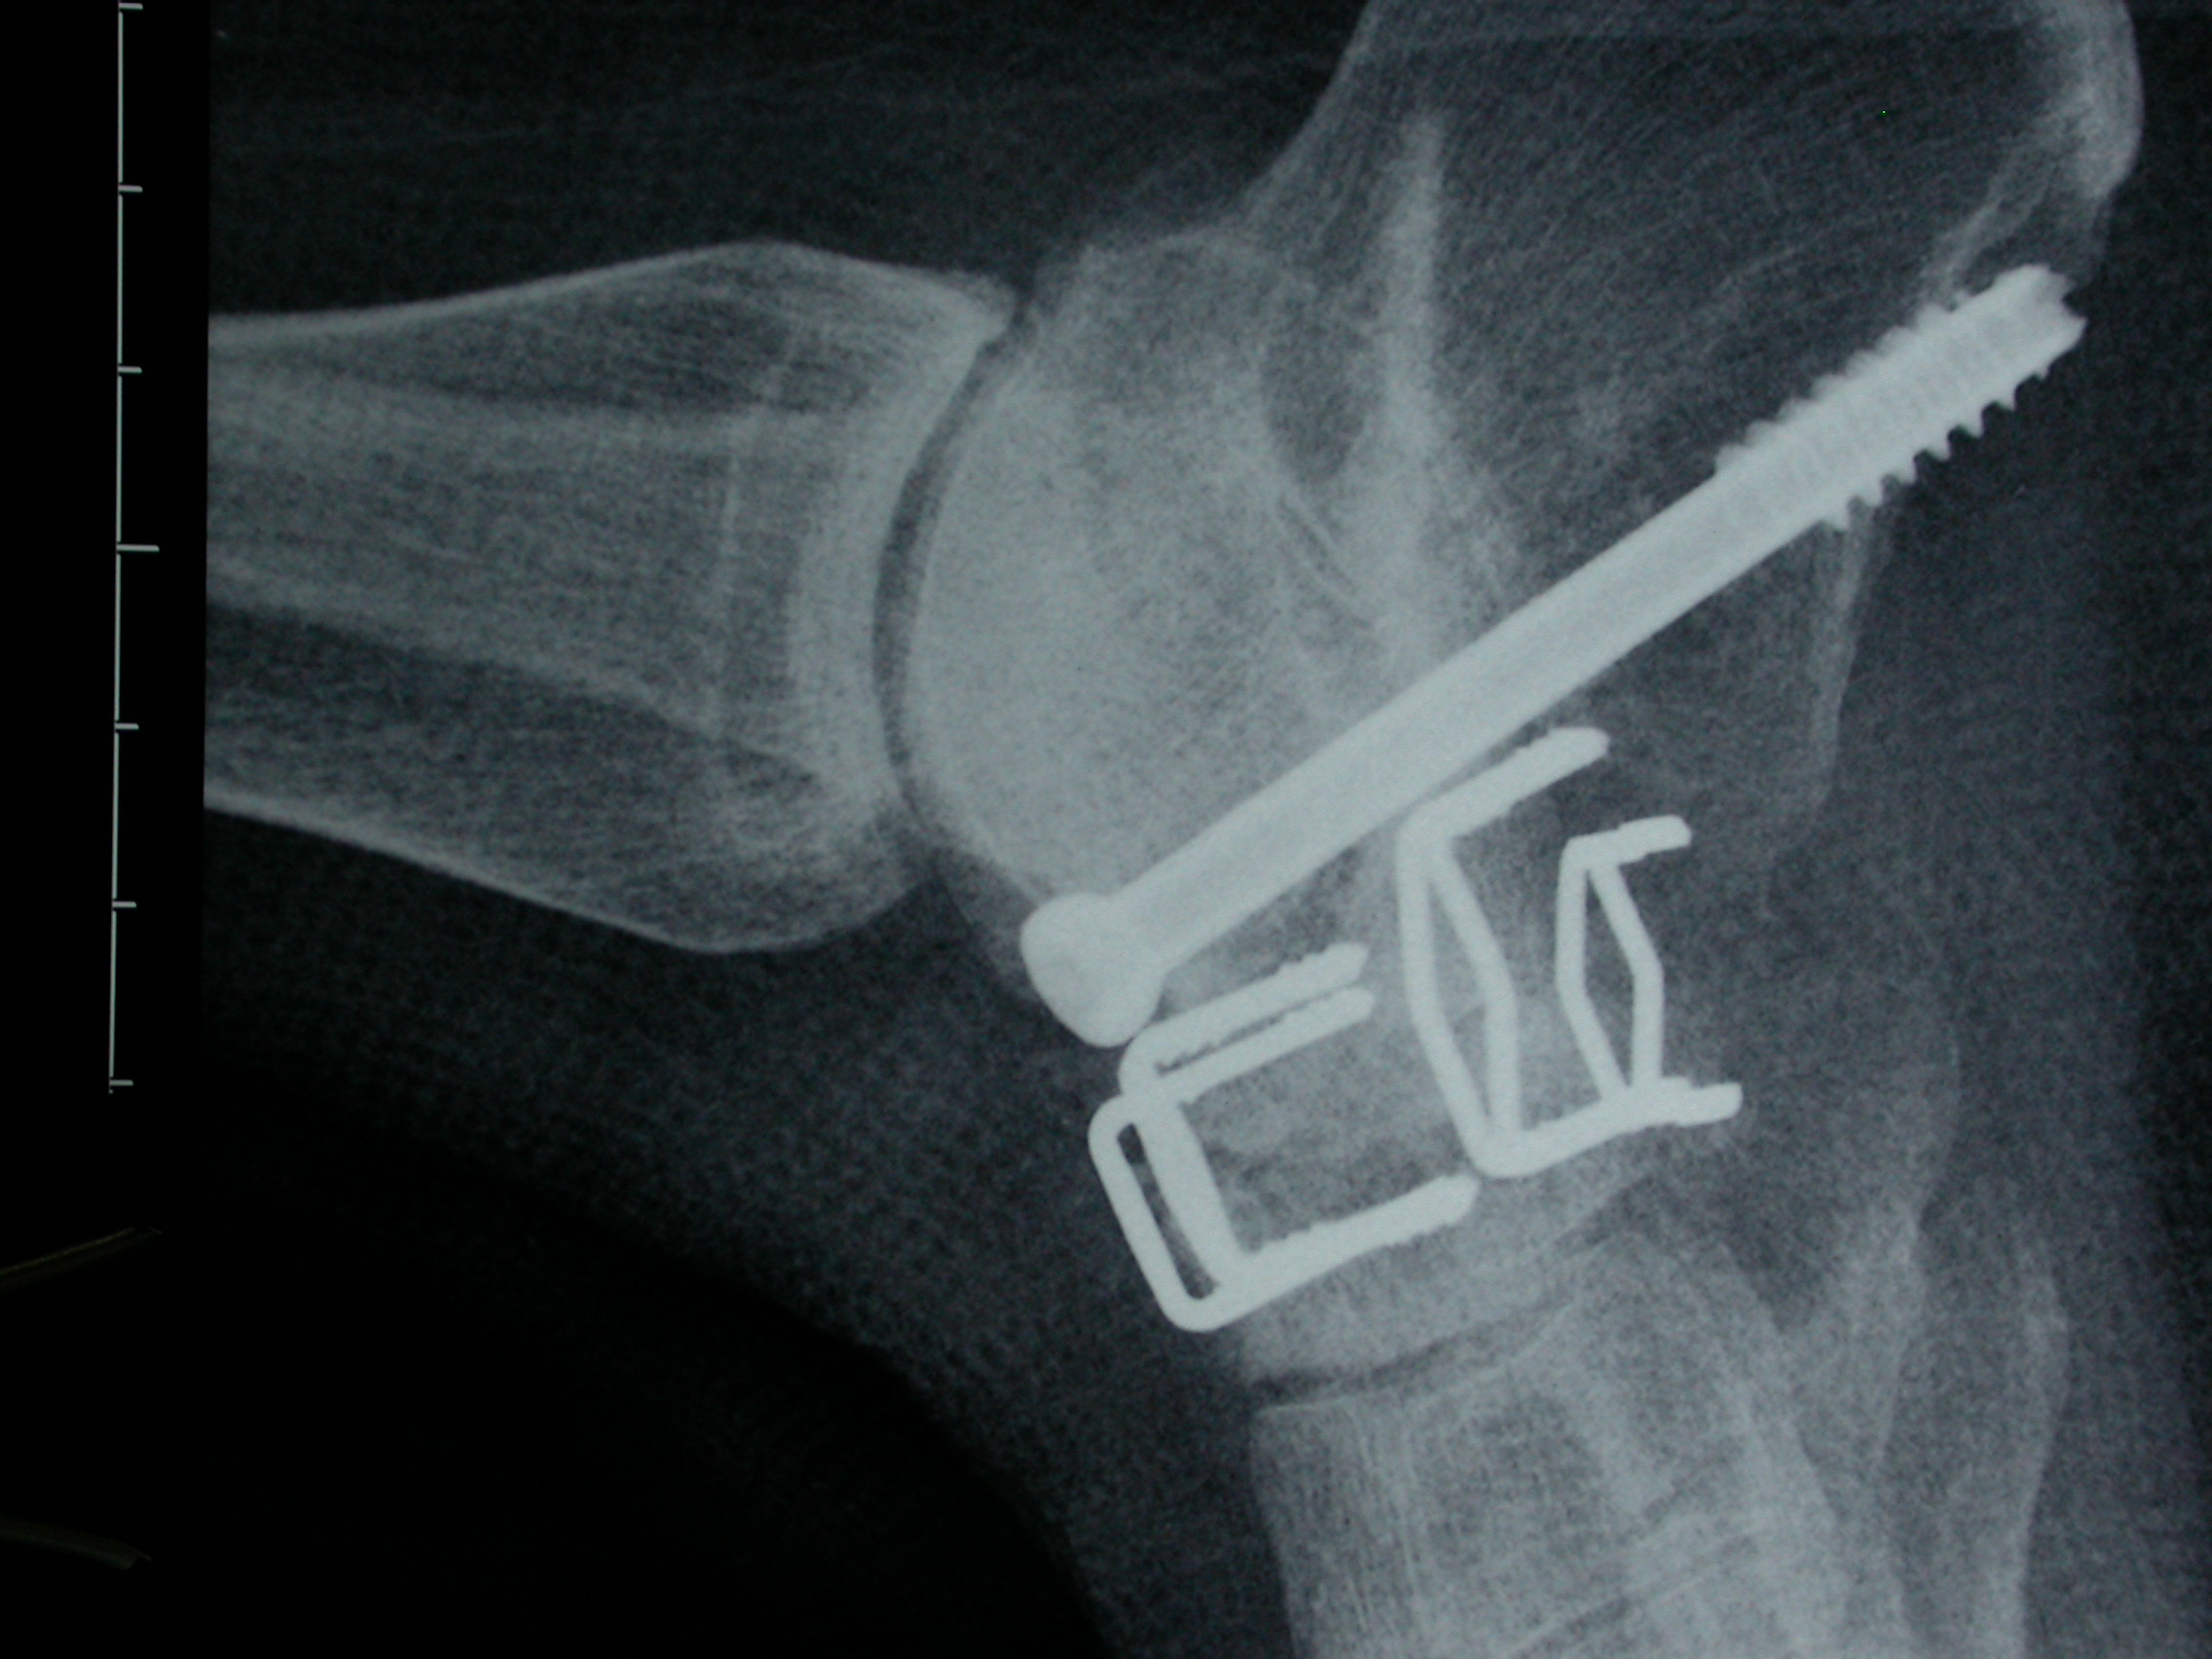

Bunion Surgery